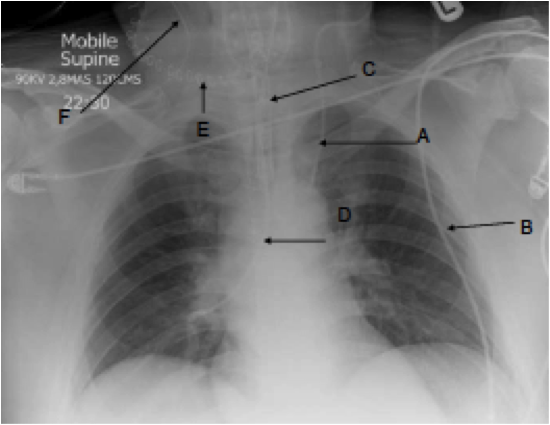

What can you see in this x-ray?

A)

B) ECG lead

C) Endotracheal tube

D) Nasogastric tube

E) Surgical staples

F)